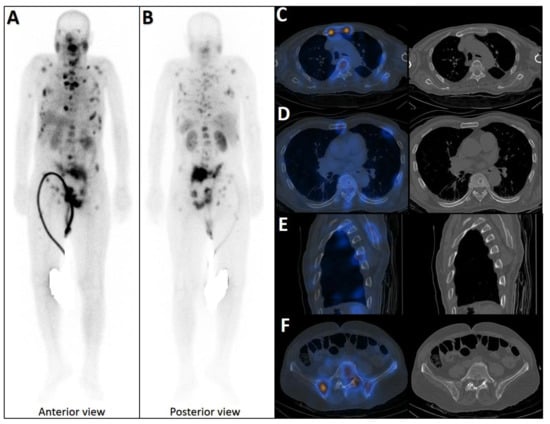

Pleuro-Pulmonary Extramedullary Plasmacytomas in Multiple Myeloma: A 15-Year Experience from a Tertiary Center

Sorina Badelita, Sinziana Barbu, Camelia Dobrea, Cerasela Jardan, Monica Popescu, Codruta Delia Popa, Claudia Toma, Larisa Zidaru, Mihai Emanuel Himcinschi, Horia Mihail Sandu, Didona Vasilache, Adelina Vlad and Daniel Coriu

Background/Objectives: Extramedullary involvement in multiple myeloma represents an aggressive disease phenotype, associated with reduced survival and an unfavorable prognosis. Thoracic manifestations are rare and remain poorly characterized in the literature. Methods: We conducted a retrospective, single-center study at the Fundeni Clinical Institute, including patients diagnosed with multiple myeloma between February 2010 and February 2025. The study cohort consisted of 34 patients with infiltration of the pulmonary parenchyma, pleura, or the presence of myelomatous pleural effusion. Diagnosis was confirmed using a combination of imaging modalities (computed tomography or magnetic resonance imaging), cytological examination, immunophenotyping, and histopathological confirmation whenever feasible. Results: Out of a total of 2012 patients with multiple myeloma, the incidence of pleuro-pulmonary extramedullary involvement was 1.6%. The median age at diagnosis was 58 years. Pleuro-pulmonary disease was present at initial diagnosis in 26.5% of cases, while 73.5% developed it at relapse. The most common presentation involved combined pleural involvement and myelomatous effusion (70.6%). Adverse prognostic markers included elevated β2-microglobulin levels (in over 80% of cases) and increased lactate dehydrogenase (LDH) in approximately 50%. Cytogenetic abnormalities such as del(17p), t(4;14), t(14;16), t(11;14), and 1q gain were identified. The median overall survival (OS) from the diagnosis of pleuro-pulmonary extramedullary disease was 16 months, with a 2-year survival rate of 25%. No patient survived beyond 5 years. The median progression-free survival (PFS) was 9 months. Conclusions: Our findings confirm the aggressive clinical course and poor prognosis of these disease manifestations, mainly when they occur at relapse. In the absence of standardized treatment guidelines, individualizing therapy and accessing novel strategies may be essential for improving patient survival.

Full article